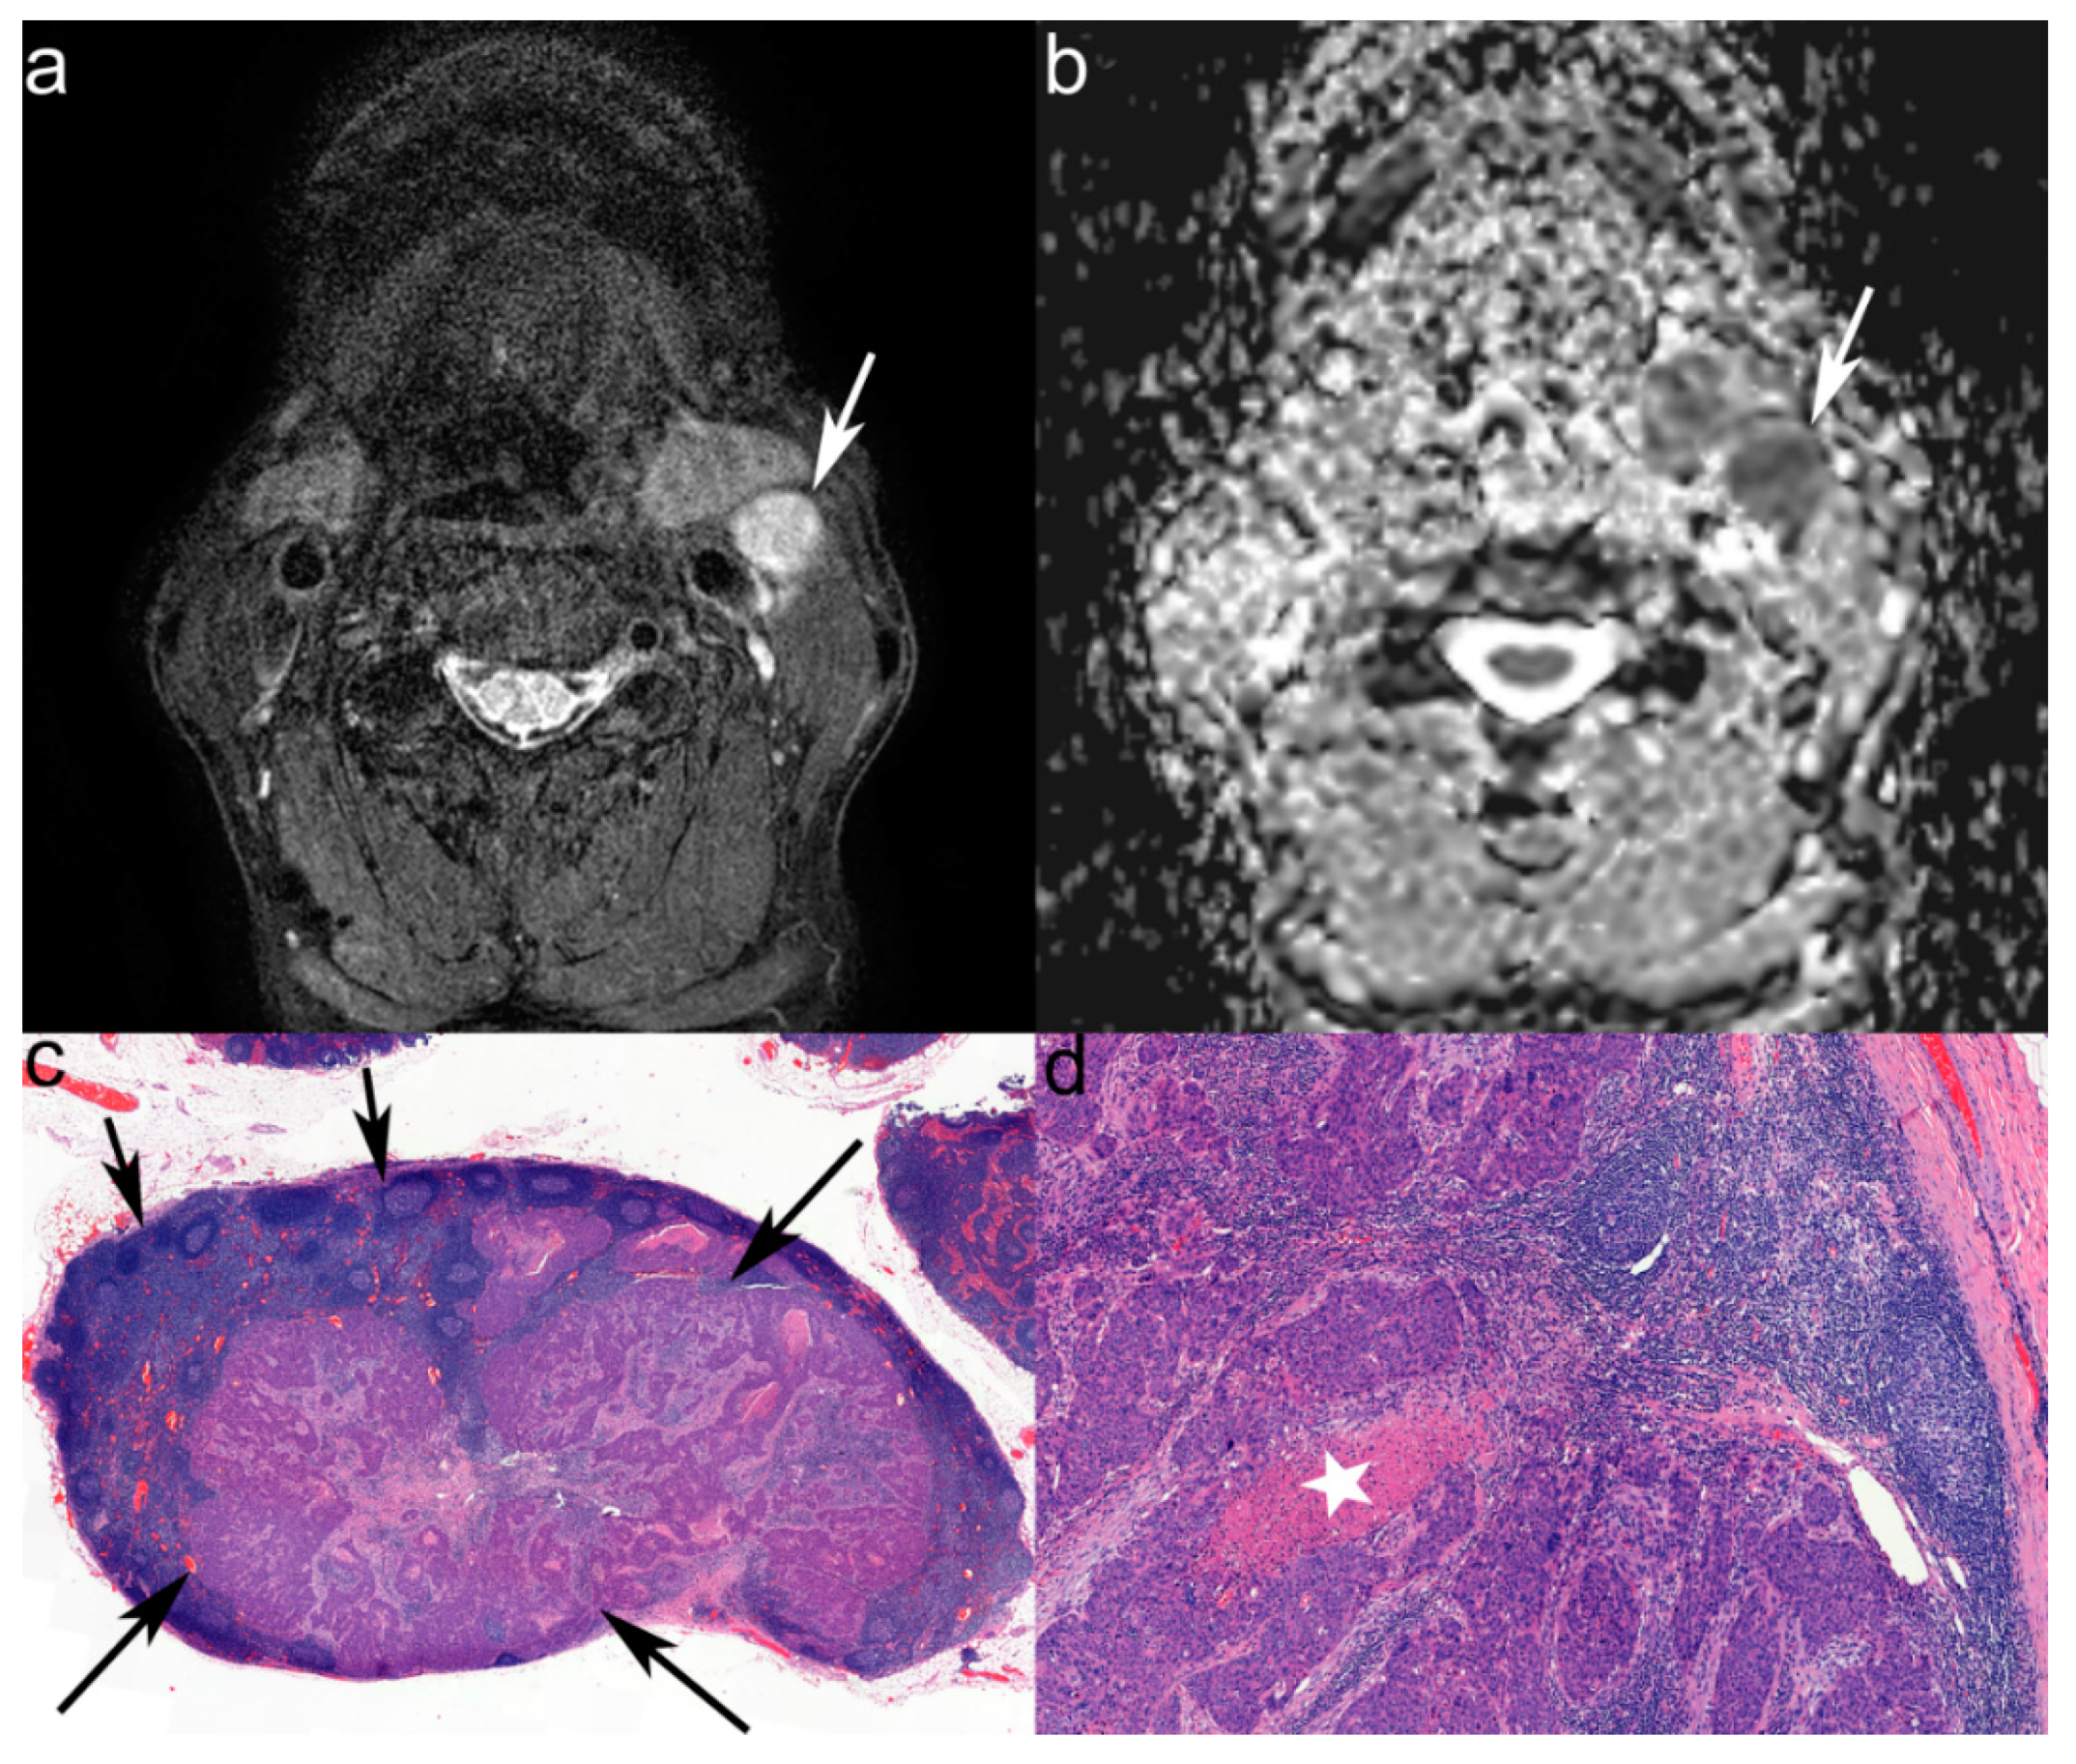

3.2. MRI Characteristics of LNs

3.3. ADC Texture Analysis